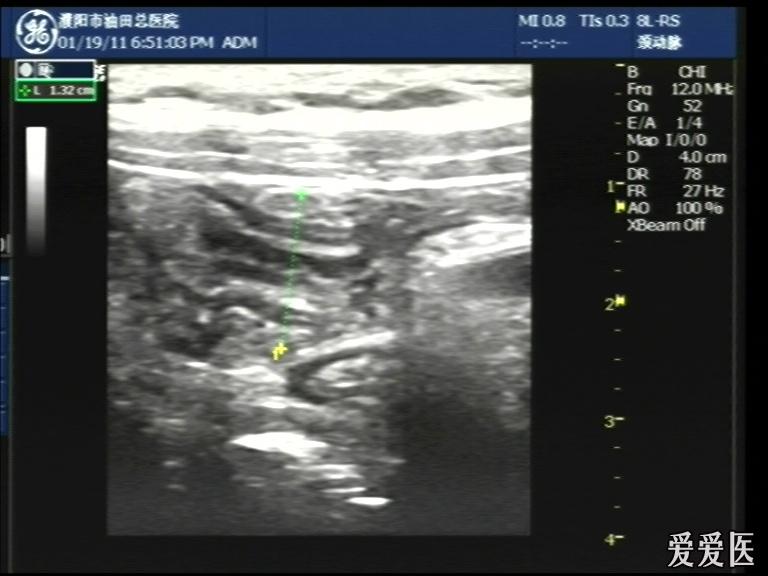

超声检查:于下腹部可见“双环征象”,双环重叠长约6mm,检查期间观察可见肠蠕动;CDFI:未见明显异常血流信号。

超声提示:下腹部双环征,考虑肠套叠可能,请结合临床

“套筒征”、“同心圆征”,很清晰,很经典!

好图,同心圆征。清晰